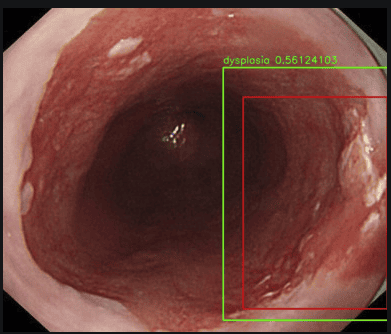

Hình ảnh loạn sản thực quản được đánh giá qua hệ thống nội soi có sử dụng trí tuệ nhân tạo AI: máy tính sẽ tìm khu trú tổn thương tự động (ô màu đỏ), đánh giá tổn thương đó có bao nhiêu phần trăm là ung thư